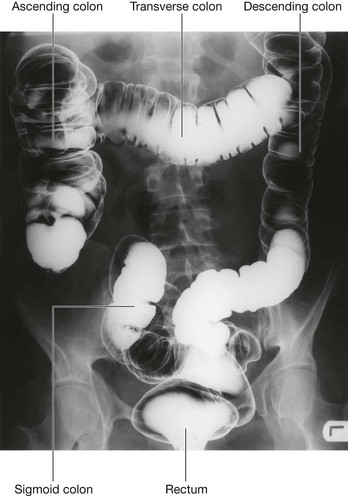

The midgut develops into the distal part of the duodenum, the jejunum, ileum, ascending colon, and proximal two-thirds of the transverse colon. A small yolk sac projects anteriorly from the developing midgut into the umbilicus.

Rapid growth of the gastrointestinal system results in a loop of the midgut herniating out of the abdominal cavity and into the umbilical cord. As the body grows in size and the connection with the yolk sac is lost, the midgut returns to the abdominal cavity. While this process is occurring, the two limbs of the midgut loop rotate counterclockwise around their combined central axis, and the part of the loop that becomes the cecum descends into the inferior right aspect of the cavity. The superior mesenteric artery, which supplies the midgut, is at the center of the axis of rotation.

The cecum remains intraperitoneal, the ascending colon fuses with the body wall becoming secondarily retroperitoneal, and the transverse colon remains suspended by its dorsal mesentery (transverse mesocolon). The greater omentum hangs over the transverse colon and the mesocolon and usually fuses with these structures.

Development of the hindgut

The distal one-third of the transverse colon, descending colon, sigmoid colon, and the superior part of rectum develop from the hindgut.

Proximal parts of the hindgut swing to the left and become the descending colon and sigmoid colon. The descending colon and its dorsal mesentery fuse to the body wall, while the sigmoid colon remains intraperitoneal. The sigmoid colon passes through the pelvic inlet and is continuous with the rectum at the level of vertebra SIII.